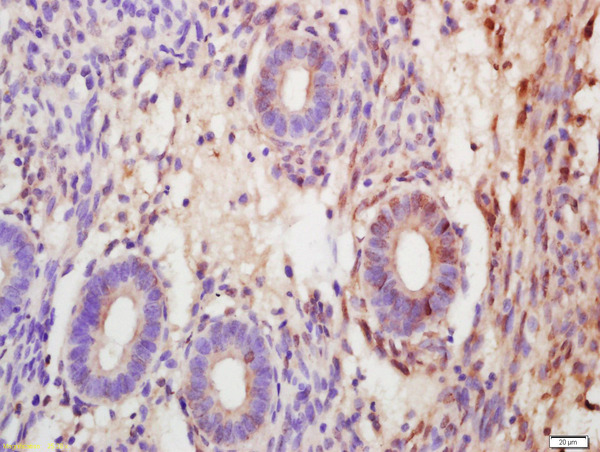

- Main image

- Experimental details

- Formalin-fixed and paraffin embedded human endometrial carcinoma labeled with Anti-SOX7 Polyclonal Antibody, Unconjugated (bs-12277R) at 1:200 followed by conjugation to the secondary antibody and DAB staining

- Sample type

- Human

- Other comments

- Placenta